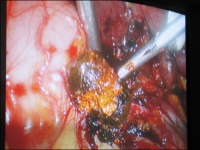

肝外胆管结石的治疗肝外胆管结石现仍以手术治疗为主。手术治疗的原则是:①术中尽可能取尽结石;②解除胆道狭窄和梗阻,去除感染病灶;③术后保持胆汁引流通畅,预防胆石再发。常用手术方法有以下几种:

1、胆总管切开取石加T管引流术:适用于单纯胆管结石,胆管上、下端通畅,无狭窄或其他病变者。若伴有胆囊结石和胆囊炎,可同时行胆囊切除术。有条件者可采用术中胆管造影,B超检查或纤维胆道镜检查,有助于减少胆石残留率。如非手术疗法不成功,症状反复发作或加重,则需手术治疗。

(2)肝内胆管结石肝内胆管结石病因复杂,但与肝内感染,胆汁淤滞,胆道蛔虫等因素有关。肝内胆管结石常合并肝外胆管结石,除具有肝外胆管结石的病理改变外,还有: